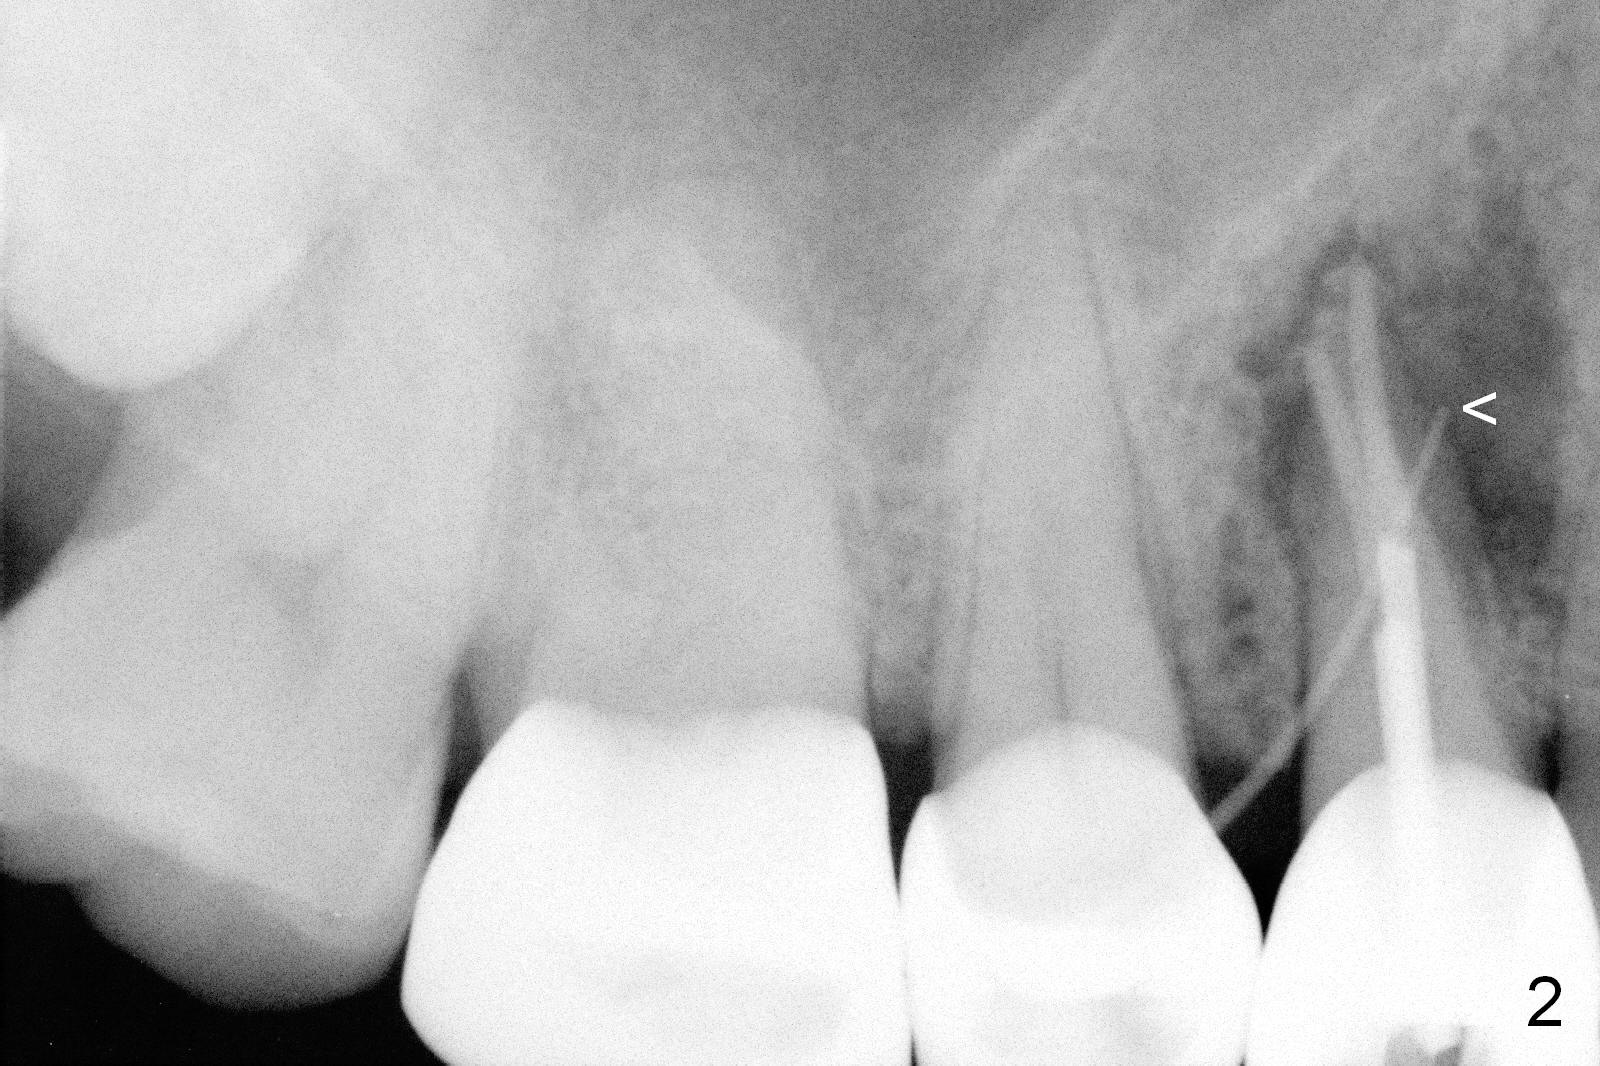

A 68-year-old man has pain and swelling associated with the tooth #5 (Fig.1). The fistula (*) is connected to the periapical radiolucency using a gutta percha (Fig.2 <). There are deep pockets distobuccal and lingual. The lingual root is found to have oblique fracture upon extraction. The distobuccal plate perforates (Fig.3). Collagen plug is placed. The buccal plate is concave (Fig.4) and socket density is low 2.5 months post extraction. Three months post extraction a 4.5x8 mm Bicon implant is placed after reamer and osteotome osteotomy (Fig.6). Bone density around the implant appears to increase 5 months post placement (Fig.7). Porcelain-fused-to-metal crown is cemented 2 weeks later. Bucco-occlusal porcelain chips 2 months post cementation. The patient decides to redo the crown. PA is taken before crown removal (Fig.8: 3 year 10 months post cementation). When a straight abutment is removed (Fig.9 A), a 15° angled abutment has to be used (Fig.10 red) for restoration.